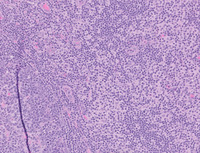

Reactive dermatopathic changes

Category: Lymph Node and Spleen: Reactive/infectious > Reactive nodal processes

Shown is a groin lymph node with dermatopathic changes. Note the increased number of paracortical histiocytes and langerhan cells seen on the right side of the image. These changes can be seen in lymph nodes draining chronically irritated skin.